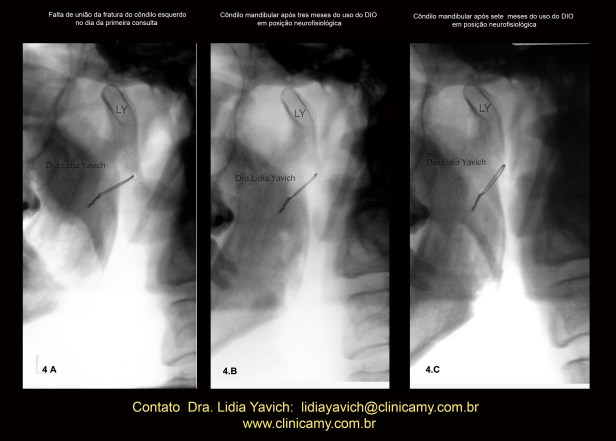

Imagem comparativa do côndilo mandibular esquerdo na primeira radiografia panorâmica do paciente no dia da consulta (4A).

Segunda radiografia panorâmica três meses após (4B)

Terceira radiografia panorâmica (4C) quatro meses após o segundo controle mostrando a melhora da posição do côndilo mandibular e a união do osso.

OBSERVAR A VERTICALIZAÇÃO DO FIO METÁLICO DA CIRURGIA

INVERSÃO DA COR da imagem comparativa do côndilo mandibular esquerdo na primeira radiografia panorâmica do paciente no dia da consulta (4A), segunda radiografia panorâmica três meses após (4B) e terceira radiografia panorâmica (4C) quatro meses após o segundo controle mostrando a melhora da posição do côndilo mandibular e a união do osso.

OBSERVAR A VERTICALIZAÇÃO DO FIO METÁLICO DA CIRURGIA.

Imagem comparativa do côndilo mandibular esquerdo na primeira radiografia panorâmica do paciente no dia da consulta (4A), segunda radiografia panorâmica três meses após (4B) e terceira radiografia panorâmica (4C) quatro meses após o segundo controle mostrando a melhora da posição do côndilo mandibular e a união do osso.